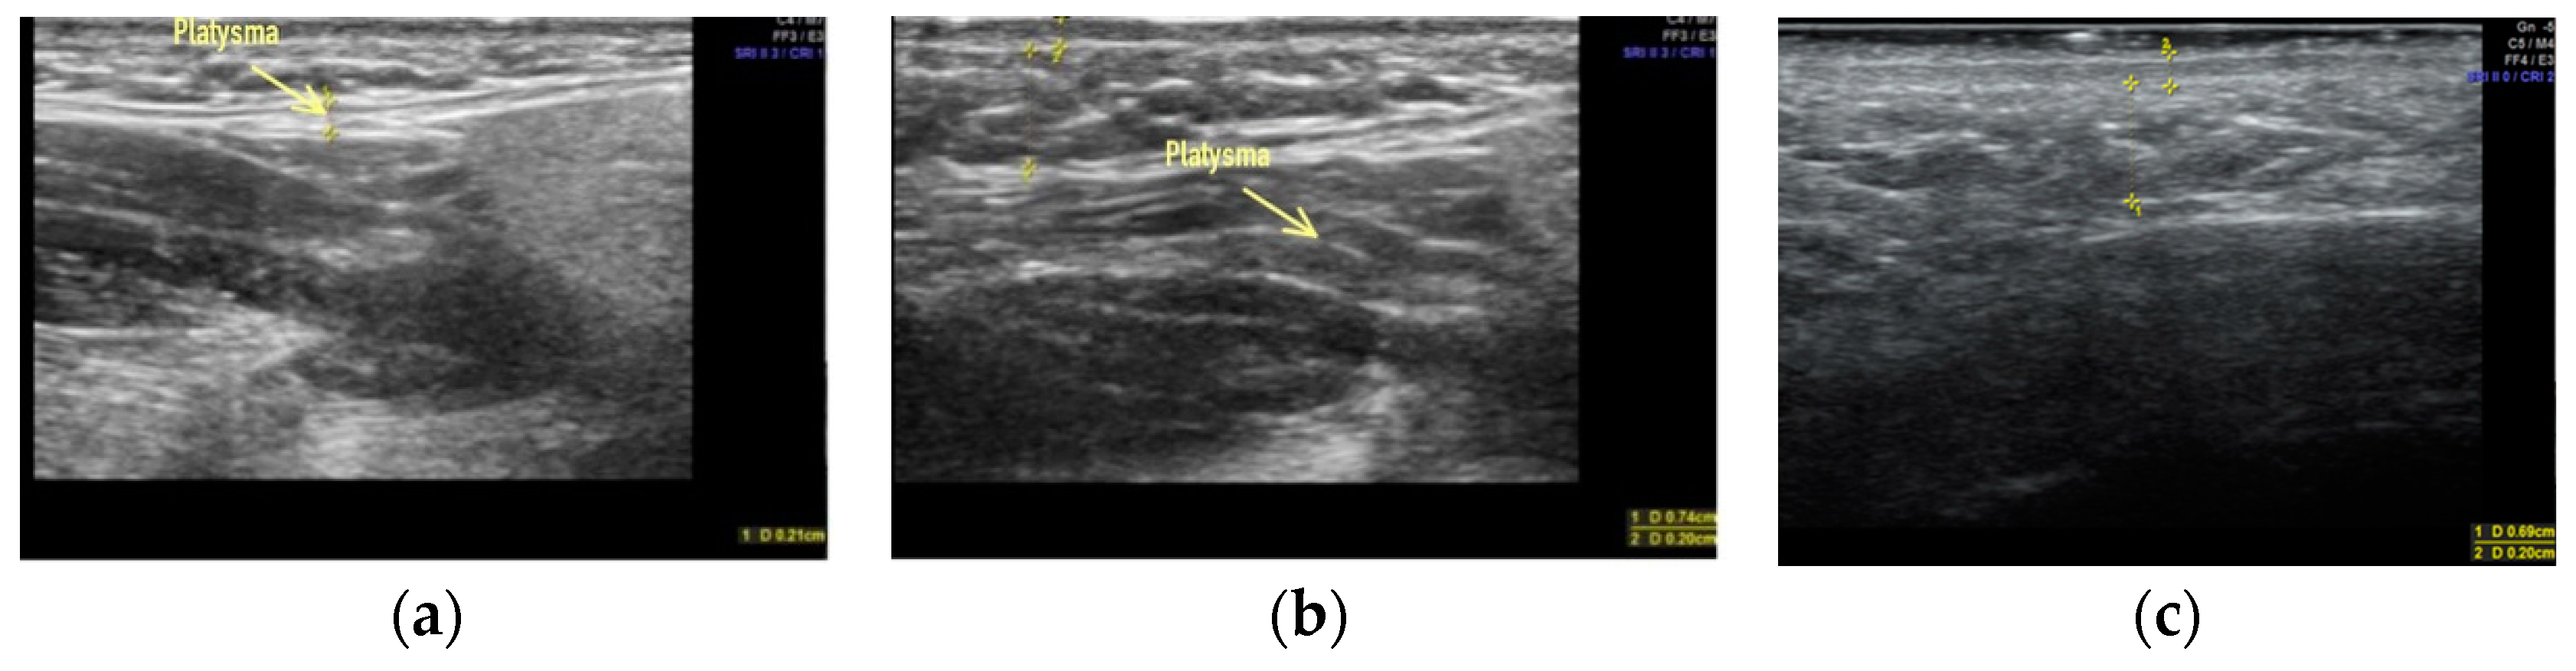

Clinical case #1. During the study, a 43-year-old female patient was examined with a 9 MHz linear transducer of soft tissues of the lower third of the face and neck without pressure, in an upright position; the skin, subcutaneous tissue, and m. platysma were visualized and the degree of their participation in the formation of deformity was estimated. Excessive accumulation of adipose tissue was determined along the contour of the lower jaw from both sides (Figure 1a,c) as well as in the submental area above and below the platysma muscle (Figure 1b).

B-mode ultrasound examination of the soft tissues of the lower third of the face and neck. A 9 MHz linear transducer. Excessive accumulation of adipose tissue in the submental area, above and below the platysma muscle (b), and along the contour of the lower jaw from both sides (a,c).

Accordingly, it is sufficient to remove this excess adipose tissue by liposuction or lipectomy to correct the contours of the lower third of the face and neck.